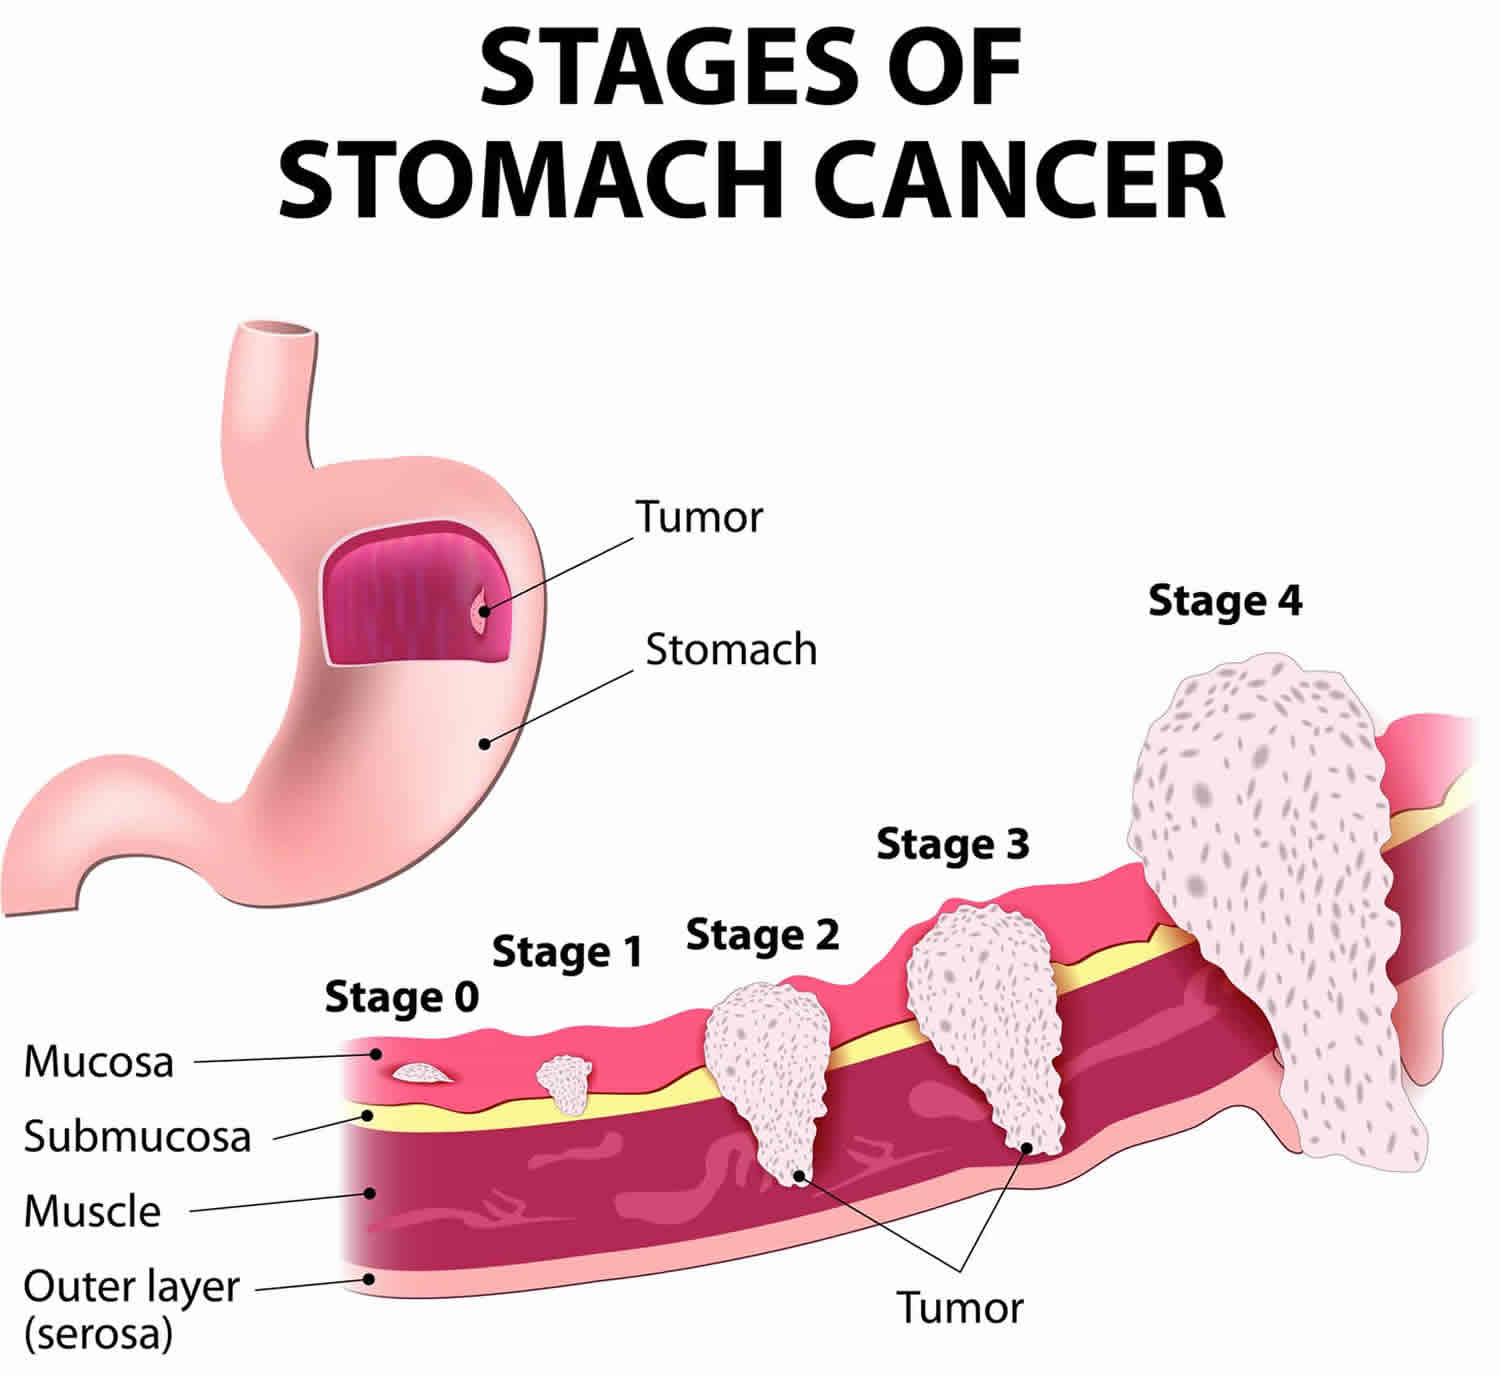

Stages of stomach cancer Royalty Free Vector Image

Stomach Cancer. Vector Illustration for Medical Use Stock Vector …

Stages Of Gastrointestinal Cancer | herxheim.de